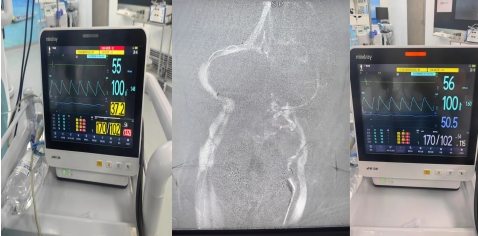

患者术中测压

术前MRV显示:左侧横窦闭塞,右侧横窦和乙状窦交界处存在狭窄。术中造影进一步明确为右侧横窦乙状窦交界处重度狭窄,狭窄程度>70%,同时左侧横窦闭塞,乙状窦纤细,与术前MRV结果相符。术中测压,经粗略计算,狭窄处近、远端压力差约为10mmHg。术中进行球囊扩张,支架置入术后造影显示,静脉窦狭窄处成形良好,可见清晰的金属支架影。